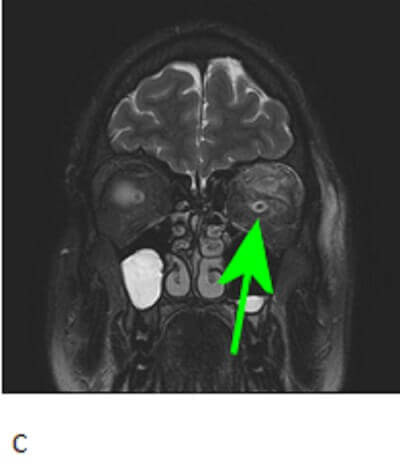

Figure 1: Red arrow. T1 pre (A) and post (B) contrast images demonstrate an ovoid T1 hypointense homogenously enhancing mass involving the superior lateral retro-orbital space with surrounding fat stranding as seen on the T2 fat saturated coronal images (C) . The mass is separate from the optic nerve (green arrow) but difficult to separate from the superior rectus.